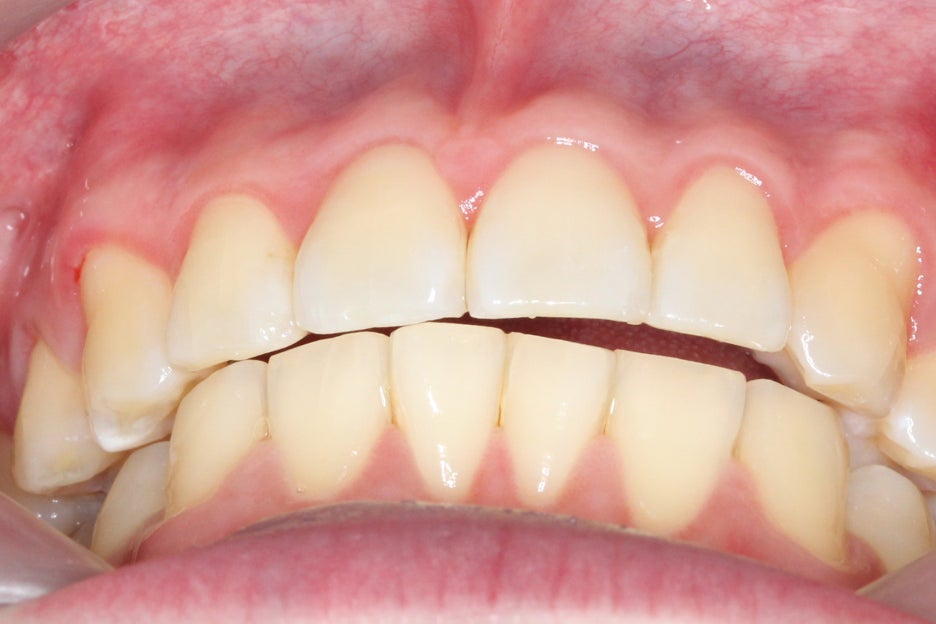

전치부의 overbite 사진을 보면

윗니부분교정 후 돌출되어 있던

중절치가 바른 각도로 교정된 것을

확인할 수 있는데요, 교정 전

11번 중절치가 아랫니에

전혀 닿지 않던 모습이 교정 후

바른 교합 상태로 바뀐 모습입니다.